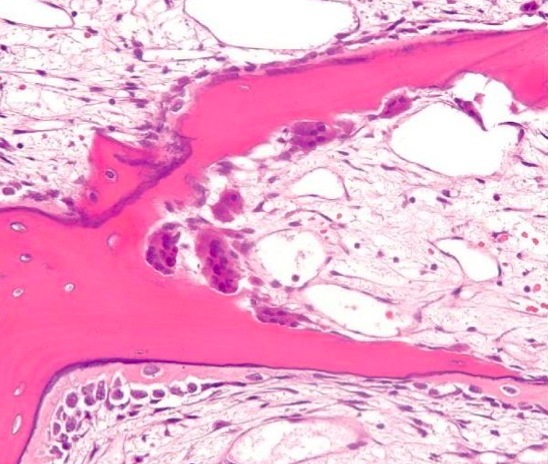

Osteitis fibrosa cystica: Brown tumour (Gross image)

Etiology

Increased PTH resulting in increased osteoclast activity.

1° - adenoma – high Ca, low PO43-

2° - renal failure – low Ca, high PO43- (opposite levels vs 1o)

3° - initially secondary cause that turned primary due to cellular adaptive change

Sx: Stones, Bones, Moans